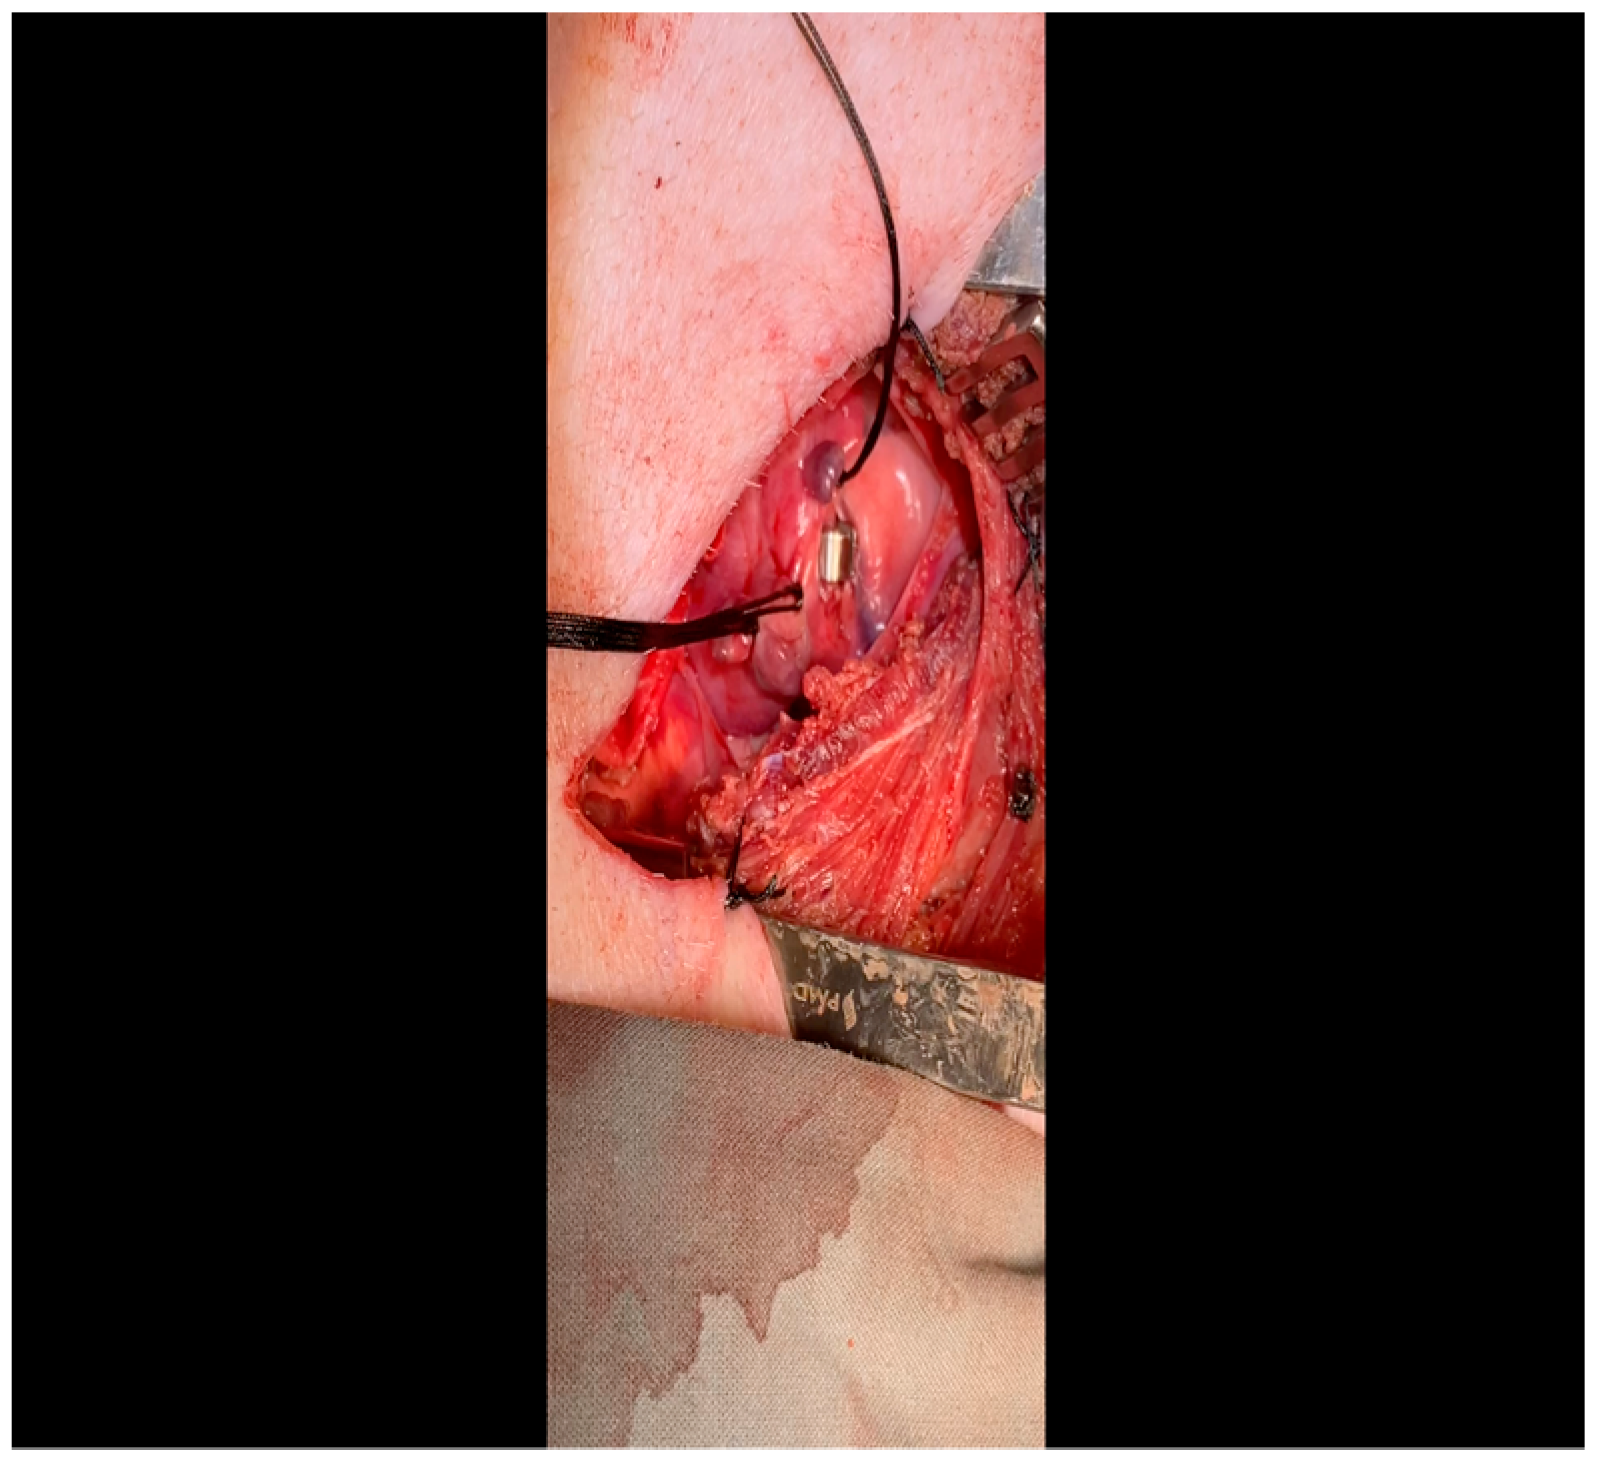

- The pericardium is opened (Figure 3) with scissors. It is important to identify and protect the phrenic nerve.

- A 3-0 silk suture secures the pericardium to the skin, elevating the heart into the surgical field and retracting the pericardium (Figure 4).

- When the ST changes return to normal, the ameroid constrictor (1.5–2.5 cm, depending on size of the left circumflex artery, with 2.25 cm constituting the most commonly used device; see Figure 8) can be placed. Prior to attempting placement, it is essential to ensure that an adequate pocket is dissected: the proximal aspect of the vessel must be circumferentially freed from surrounding tissue, and the junction with the left main coronary artery should ideally be visualized. Small bridging veins may require clipping and division, and fine, non-absorbable suture (we use 6-0 polypropylene) should be made available in the event that vascular repair or ligation of venous bleeding is required. The device should be lubricated prior to placement to ease placement onto the artery. We have found that using Allis forceps to grasp the metallic outer casing of the ameroid permits a firm grip despite lubrication. An assistant may additionally use DeBakey forceps to retract surrounding epicardial tissue out from the intended ameroid pocket. Once an adequate pocket is visualized, the vessel loop is removed, and the ameroid is placed onto the artery. Forceps or a finger may be used to stabilize the ameroid while it is being placed, and the keyhole is rotated so that it faces outward (Figure 9). This will permit the device to remain in situ despite the beating of the heart (Figure 10), whereas the heartbeat may dislodge the device if it is facing in the opposite direction. If there is excessive manipulation of the left circumflex artery during this procedure, heparin will be given IV to help prevent thrombus formation. If there is spasm, topical nitroglycerin solution will be applied to the artery directly.